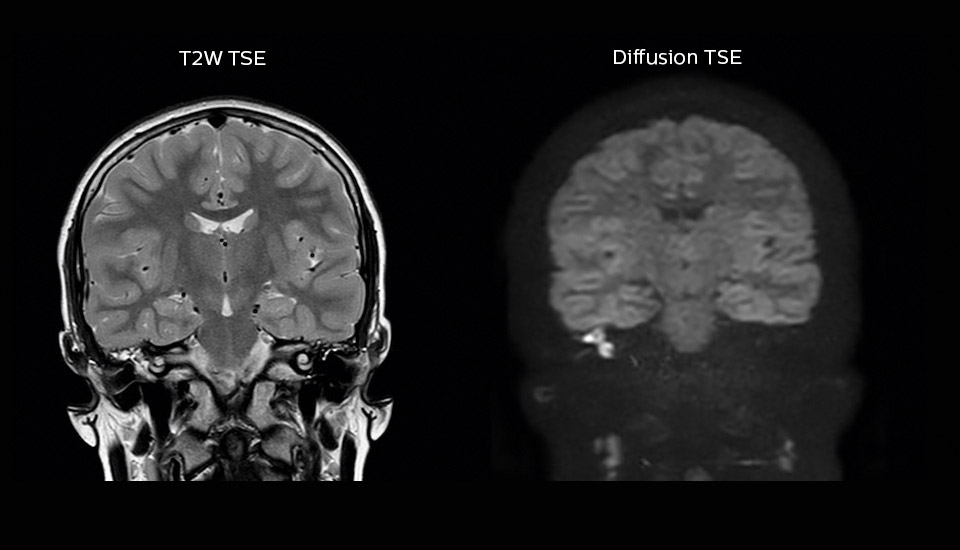

“We also love MultiVane XD for motion reduction in imaging. We find this a huge step forward. We use it in the head, and of course in the upper abdomen, and the images are outstanding most of the time. And it can be combined with dS SENSE parallel imaging for speed.” “We have compared image quality of FLAIR with MultiVane XD versus FLAIR without MultiVane XD. In 15 of the 40 patients studied, we saw motion artifacts on plain FLAIR brain images. The FLAIR images with MultiVane XD were motion-free in 39 of 40 patients and showed slight motion artifacts in only one patient.”